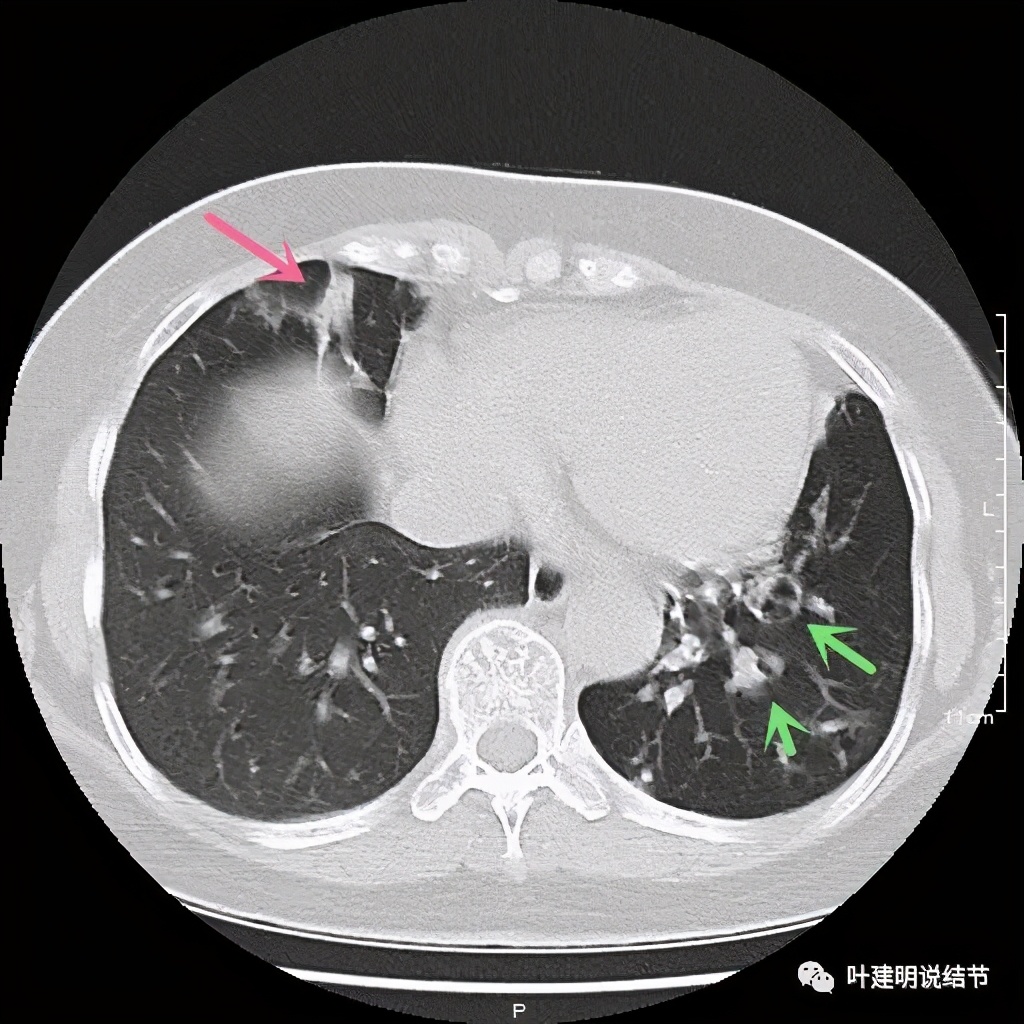

上层见病灶偏实性密度,边缘不光滑

上图见病灶为实性,中间有小空洞,边上有血管进入病灶,靠后侧有棘突样

上图示病灶边缘不光滑,中间有小空洞

上图见病灶边上有血管

上图示病灶血管征较明显,有微小血管从不同方向走向病灶